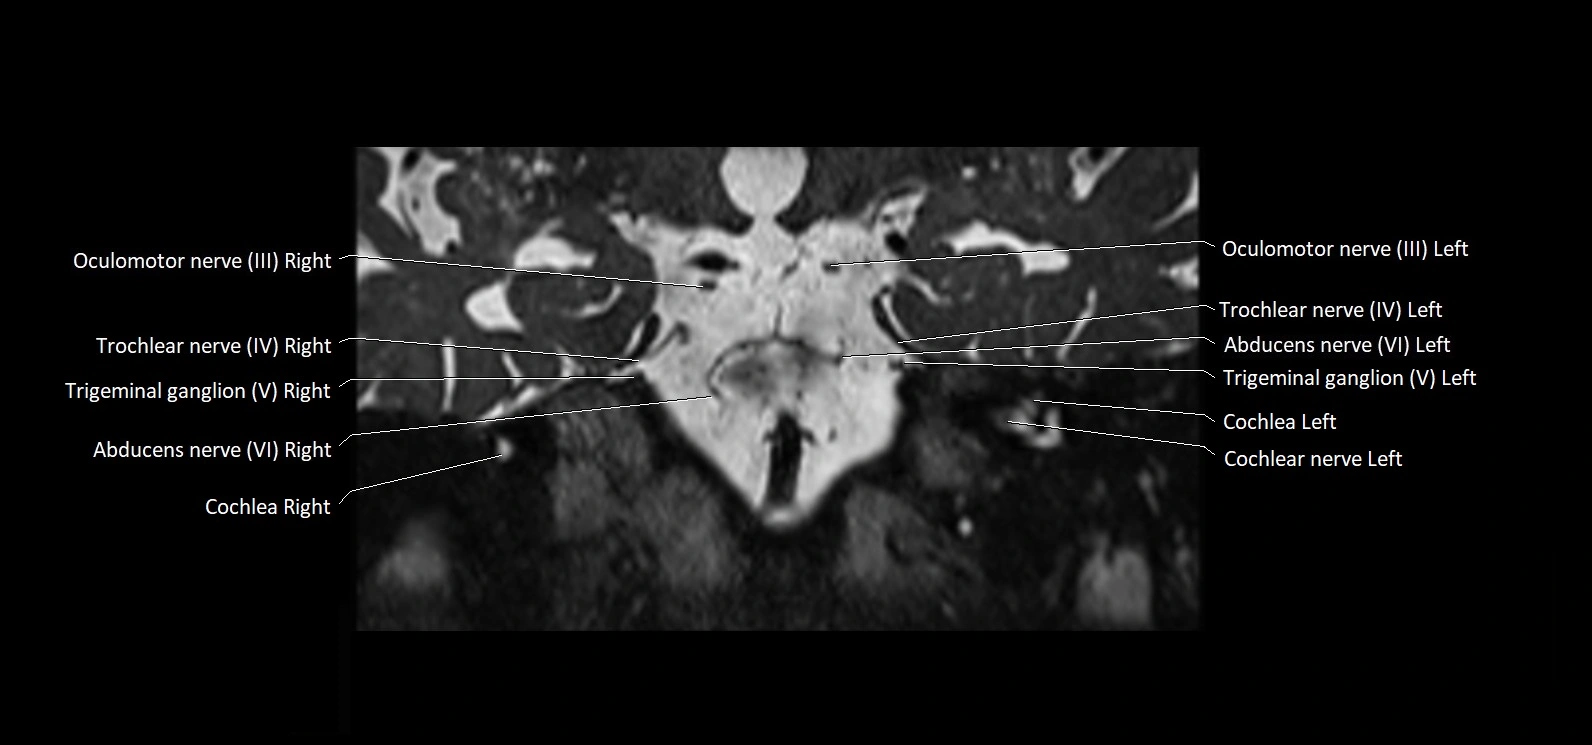

MRI images

image